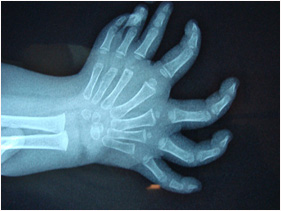

mirror hand